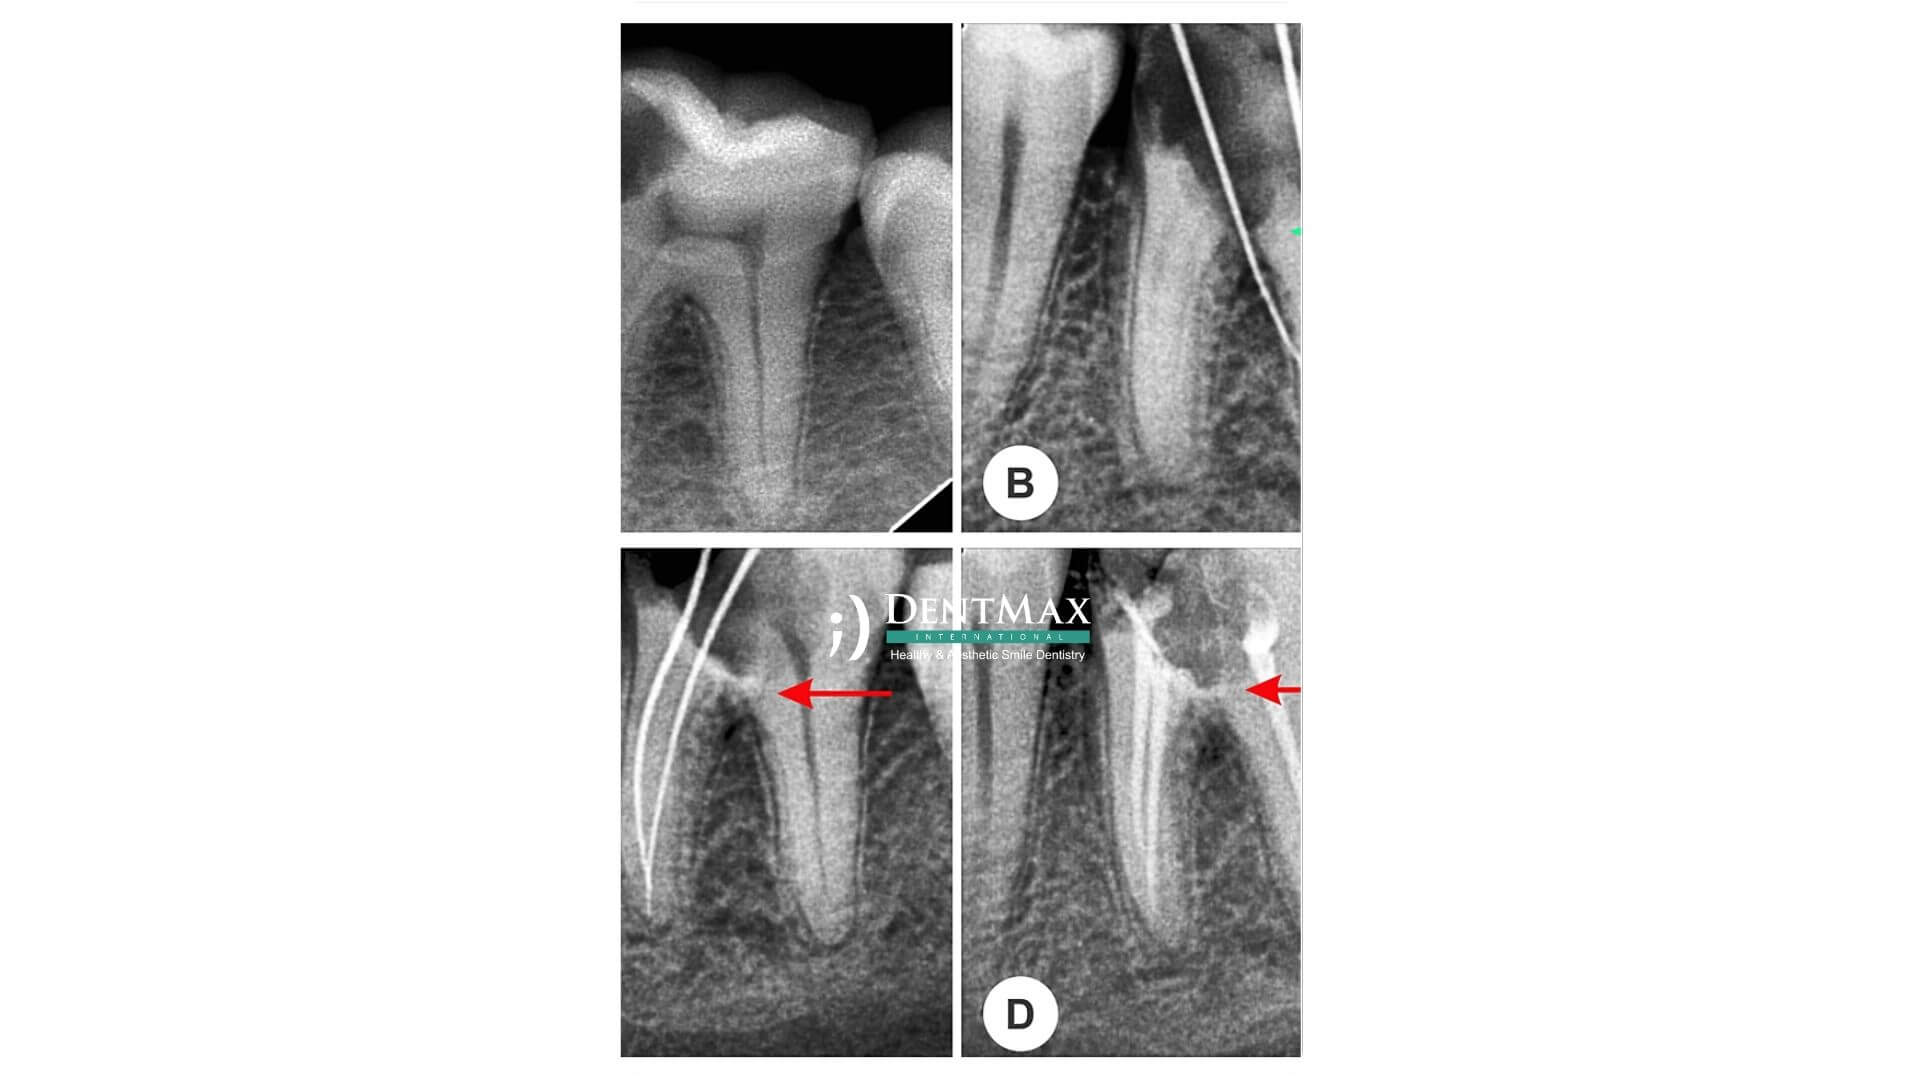

MTA-supported root canal treatment is an advanced endodontic technique used to preserve the vitality of the tooth in cases of deep decay or trauma. By applying a biocompatible material called MTA (Mineral Trioxide Aggregate), the treatment can prevent full root canal therapy and help the tooth remain functional and alive. At DentMax, this approach is particularly beneficial for younger patients and in situations where preserving the natural pulp is a priority.

It is an alternative to traditional root canal therapy where MTA is applied to protect exposed pulp tissue, allowing the tooth to remain vital and functional.

MTA is placed over the exposed or inflamed pulp, followed by sealing the area with a permanent restoration. No full canal cleaning is required in appropriate cases.

This treatment is ideal for early-stage pulp exposure, trauma-related pulp exposure, or in young patients where root development is incomplete.

MTA is biocompatible, seals effectively, promotes healing, and prevents infection — ideal for preserving pulp vitality and long-term tooth function.